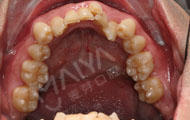

第一次试戴隐形牙套,戴隐形牙套就像戴隐形眼镜一样,刚开始不熟悉,后面就会很好戴,因为是试戴,江洋主任给我示范了好几次,我自己也试着摘戴好几遍,江洋主任真的很耐心,点赞,一共53副,然后一到两周换一副,要带好久啊,不过好期待矫牙后整齐的牙齿!

主任给我做了矫牙方案设计,这是3D隐形矫牙动画预览, 显示牙齿不齐的动画,提前预知矫牙后效果,每一步都可以看到矫牙后的牙齿形态,真的很安全放心。让我矫牙过程中一点都不担心会不会矫正会出现其他问题。